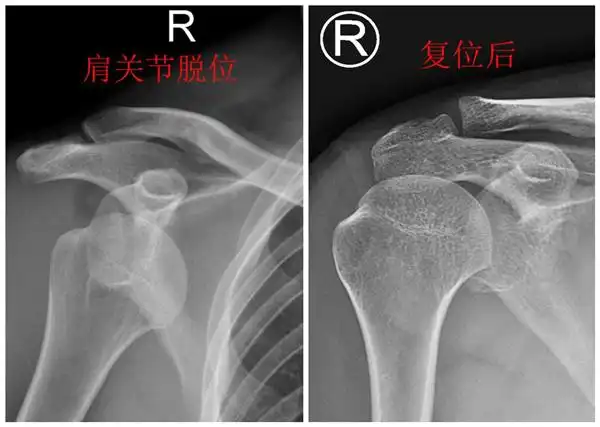

陈旧性肩锁关节脱位

肩关节半脱位

视频教学:简单实用"外展外旋法"复位肩关节前脱位